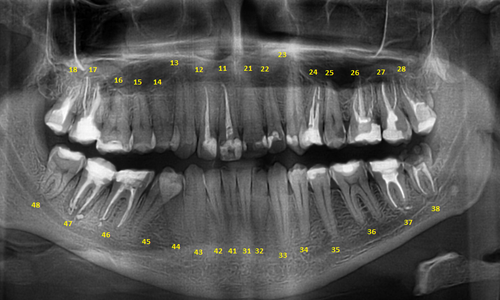

Дентальные снимки и диагностика кариеса